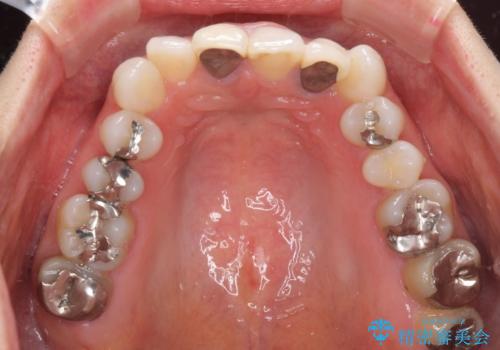

- 20年ほど前に被せた前歯のメタルボンドクラウンの色合いを気にして来院された患者様です。

2歯をオールセラミッククラウン(ジルコニアクラウン)にて補綴することとしました。

裏打ちが金属の場合、どうしても金属色を遮蔽しないとならないため、透明感のない色合いとなってしまいます。

土台の金属はグラスファイバーを含有したものに、クラウンの土台は強化セラミックとすることで、自然な前歯に仕上がりました。